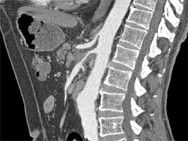

- 单项选择题根据所提供的图像,最可能的诊断是 ( )

A、淋巴瘤

B、腹膜后纤维化

C、胰腺癌

D、肝癌

E、以上都不是